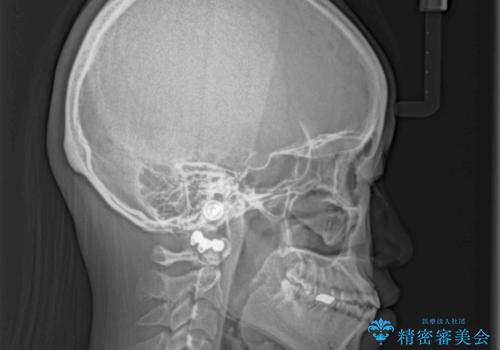

- 上下の前歯の隙間を気にして来院された患者様です。

インビザラインを用い、上下歯列のスペースを閉じていくこととしました。

治療期間中は奥歯がほとんど咬めない状態が続き、食事に大変苦労されました。

最終的には隙間もしっかりと閉じ、奥歯も咬みやすい状態でしあげることができました。